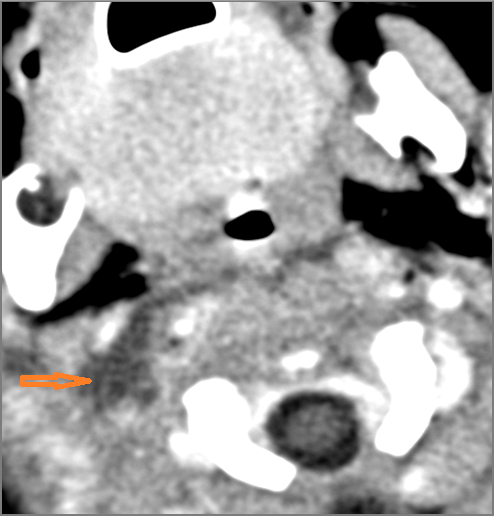

There is suppurative cervical lymphadenopathy. [Yes/No]

If there is suppurative cervical adenopathy the purulent material outside the lymph node(s) capsule(s). [Yes/No]